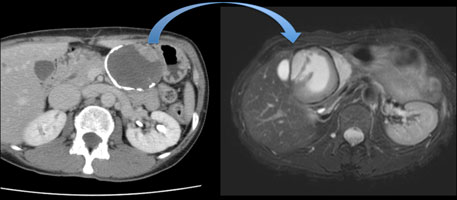

【12月スーパーSALE 15%OFF】 解答・解説】膵頭部腫瘍を指摘された60歳代男性|実践!画像診断 健康・医学の詳細情報

解答・解説】膵頭部腫瘍を指摘された60歳代男性|実践!画像診断。Amazon.co.jp: 見て診て学ぶ膵腫瘍の画像診断 : 大友 邦, 木村。症例1:診断と解説。質の高い『膵臓がん検診 (ドック)』のすすめ -うまい秘訣は。「膵腫瘍の画像診断 : 見て診て学ぶ」木村 理定価: ¥ 12000目立つ汚れなし名前印鑑あり消させていただく予定です!#木村理 #木村_理 #本 #自然/医療・薬学・健康